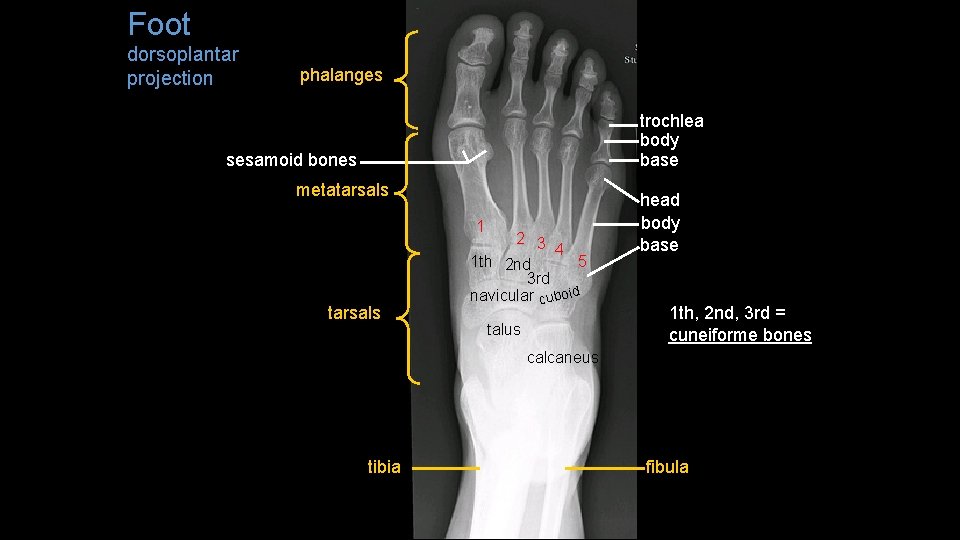

Foot dorsoplantar projection phalanges trochlea body base sesamoid bones metatarsals 1 tarsals 2 3 4 1 th 2 nd 5 3 rd navicular cuboid talus head body base 1 th, 2 nd, 3 rd = cuneiforme bones calcaneus tibia fibula